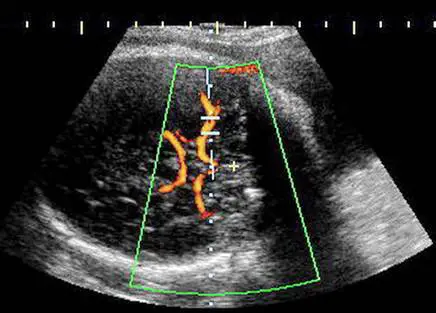

22歲孕婦,G4P1SA2,妊娠32週,接受杜卜勒(Doppler)超音波檢查,結果如圖所示,檢查名稱為何? 圖片描述

從彩色Doppler影像可見:

• 掃描平面為胎兒頭顱的橫切面,定位在顱底區域,可見蝶骨小翼(sphenoid wing)陰影。

• 在腦底中央呈現圓環形血流訊號,即「Willis環」(circle of Willis),其左右兩側分岔向外的是主要分支。

• 血流顏色由近似探頭方向流入顯示為紅色/黃色,高速血流已出現部分aliasing mosaic現象,符合動脈血流特徵。

• 樣本採集點位於Willis環近端的側向分支,即MCA的近端(proximal segment),波形最具重現性。

以上特徵與middle cerebral artery Doppler評估的典型擺位相符。